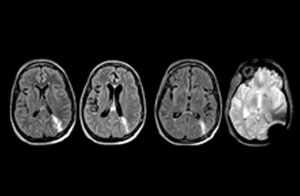

Guidance on appropriate use of MRI

A range of protocol sheets was developed to help ensure that referring physicians order the most appropriate MRI exam. The optimized MRI protocols also include 3D contrast-enhanced imaging, allowing neurosurgeons to comfortably use the isotropic data in the operating room while performing stereotaxic surgery.